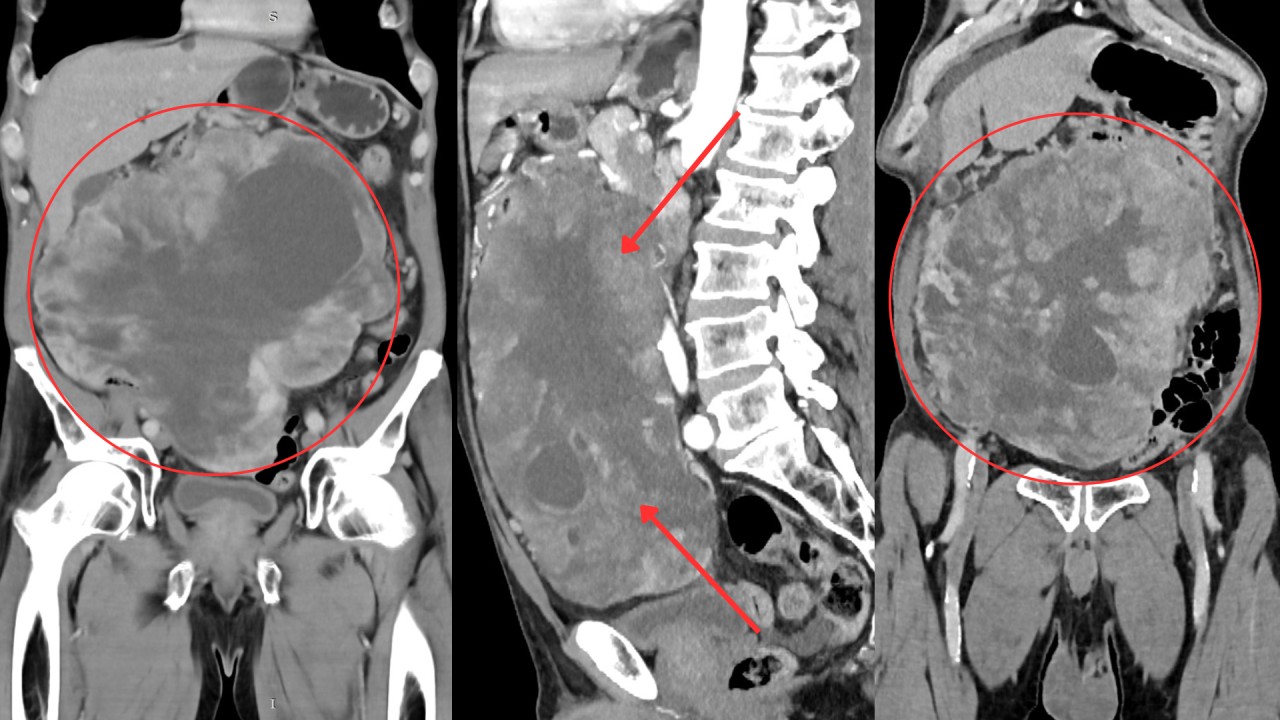

ՈՒԱԿ մասնագետը նույնպես հանդես է եկել զեկույցով և ներկայացրել ՈՒԱԿ դիմած 52-ամյա կնոջ մոտ շատ հազվադեպ հանդիպող (1 %) կրծքագեղձի բարորակ գոյացության դեպքը։

Դեպքի առանձնահատկությունը կայանում էր նրանում, որ կլինիկական և ռադիոլոգիական պատկերների միջև եղել է տարբերություն։ Ուռուցքը կլինիկորեն ունեցել է չարորակի բոլոր դրսևորումները, սակայն ռադիոլոգիապես այն որակվել է բարորակ։ Հետագայում հյուսվածաբանորեն հաստատվել է գոյացության բարորակ լինելը։